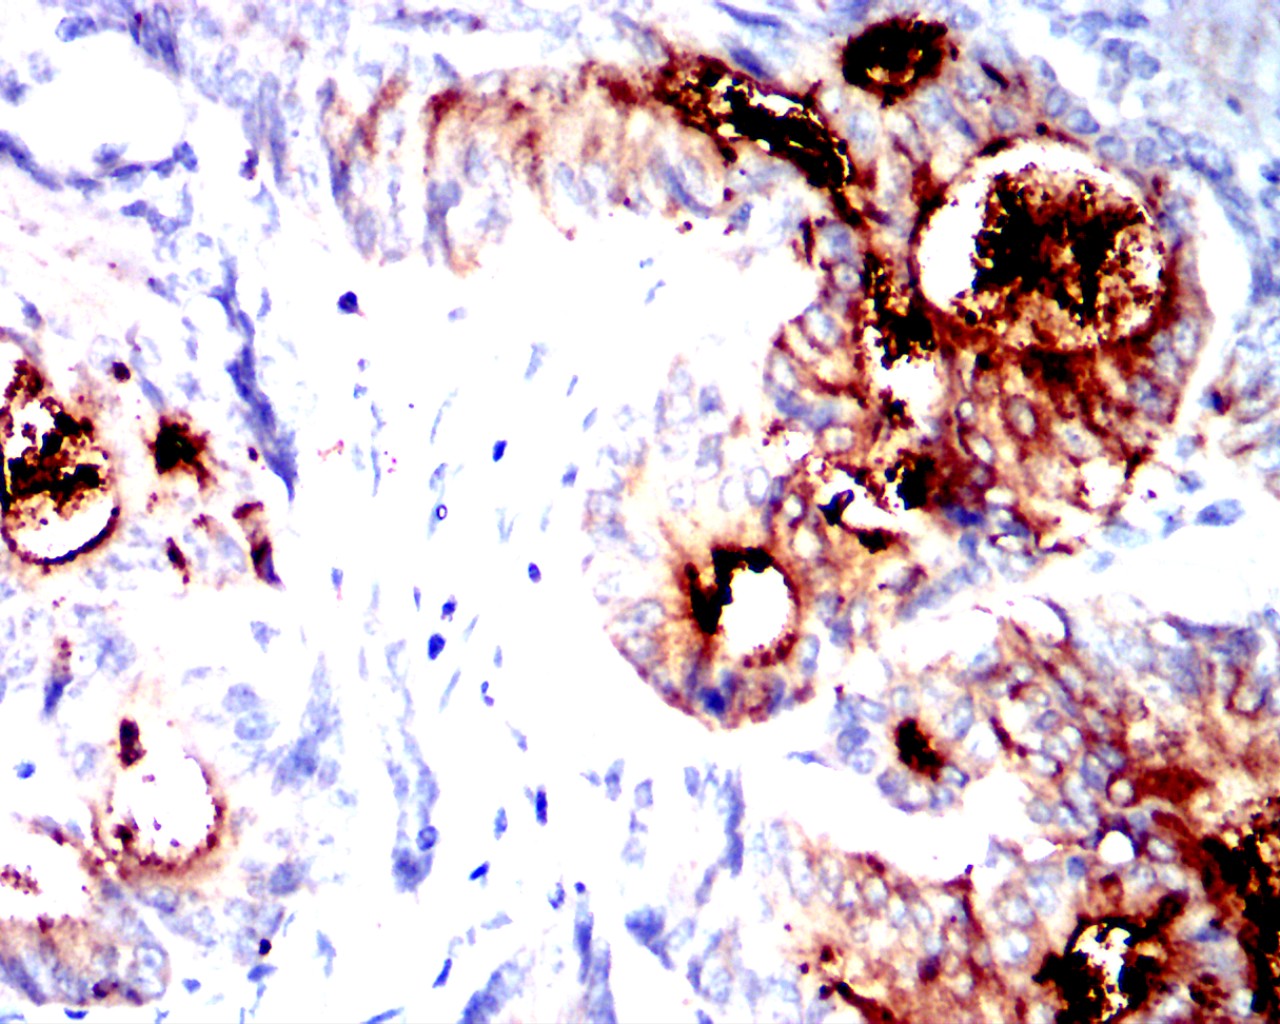

Immunohistochemical analysis of paraffin-embedded human breast cancer tissues using CEACAM5 mouse mAb with DAB staining.

应用详情:IHC:1/200-1/400

CEACAM5 Mouse mAb

别名:CEA;CD66e

计算分子量:76.8kDa